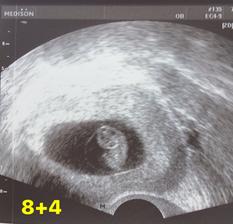

@verryk dekuji moc. Dnes byla kontrola a vse v poradku. Mi i je o 3 dny napred tedy 11+0 a mela sem byt 11+4